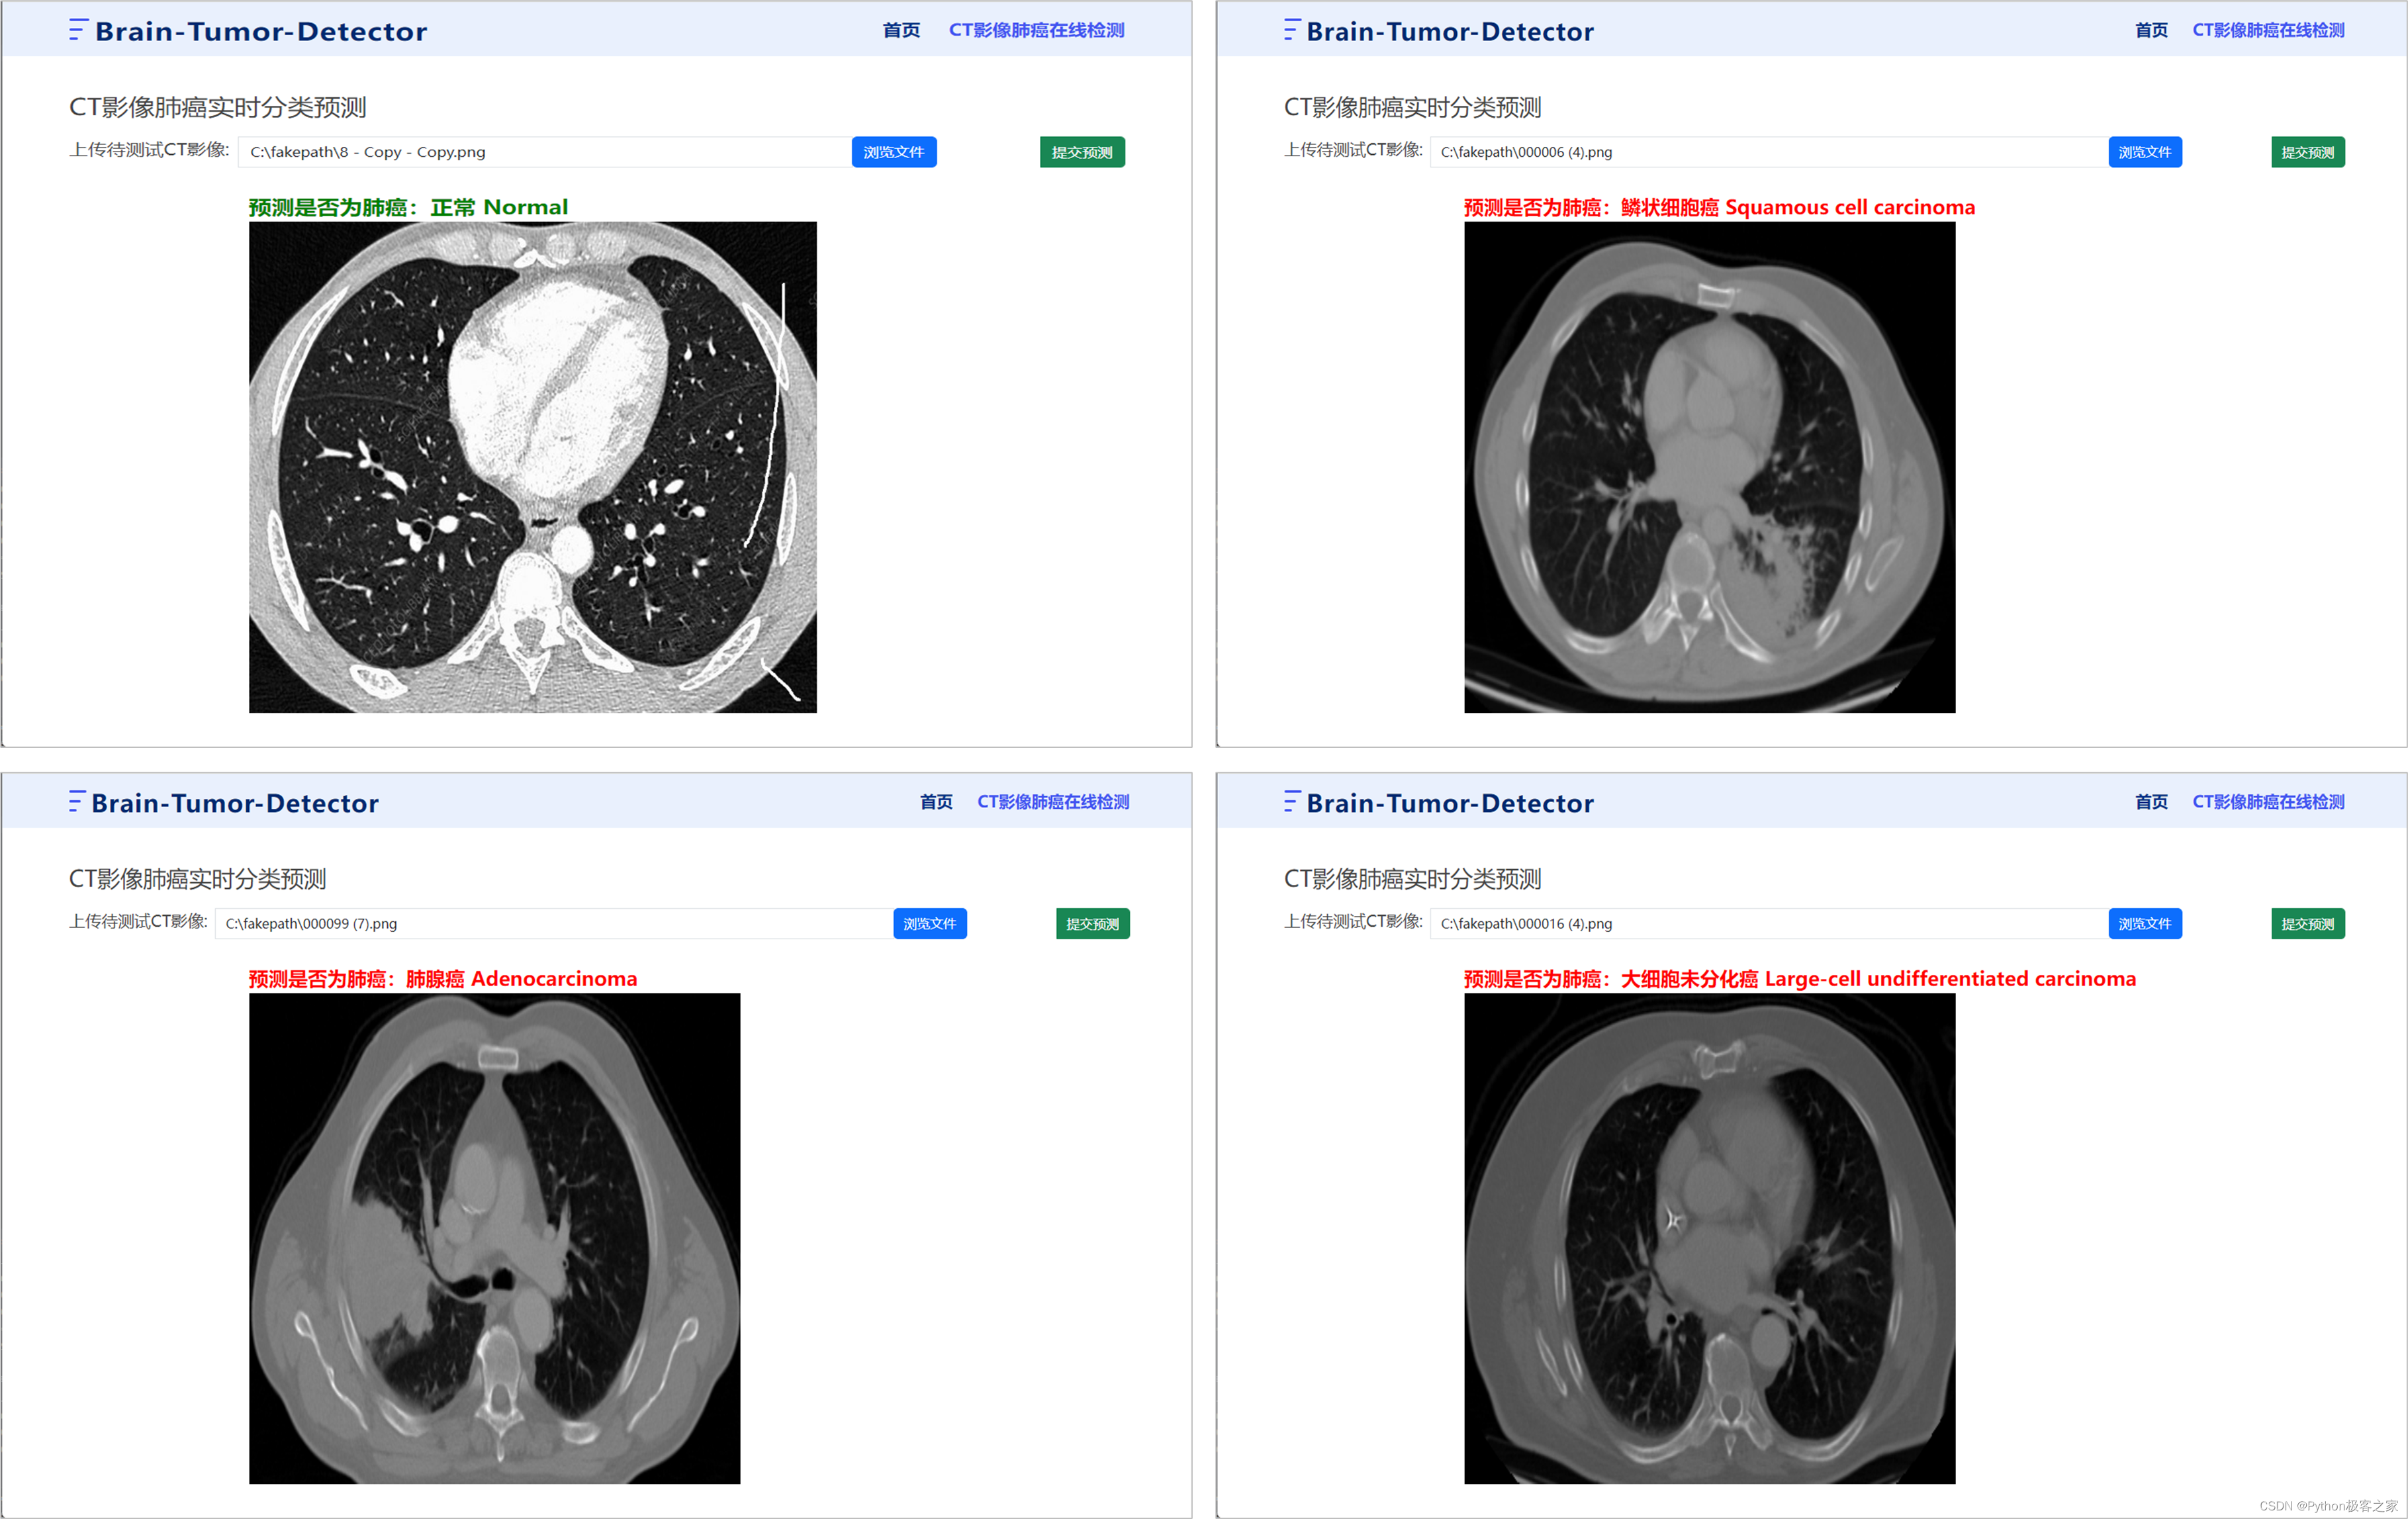

6. CT影像肺癌检测识别系统

6.1 系统首页

6.2 肺癌在线检测

通过上传肺癌的CT影像,点击提交预测,后台加载训练好的模型,预测是否换有肺癌及其肺癌的具体类型: